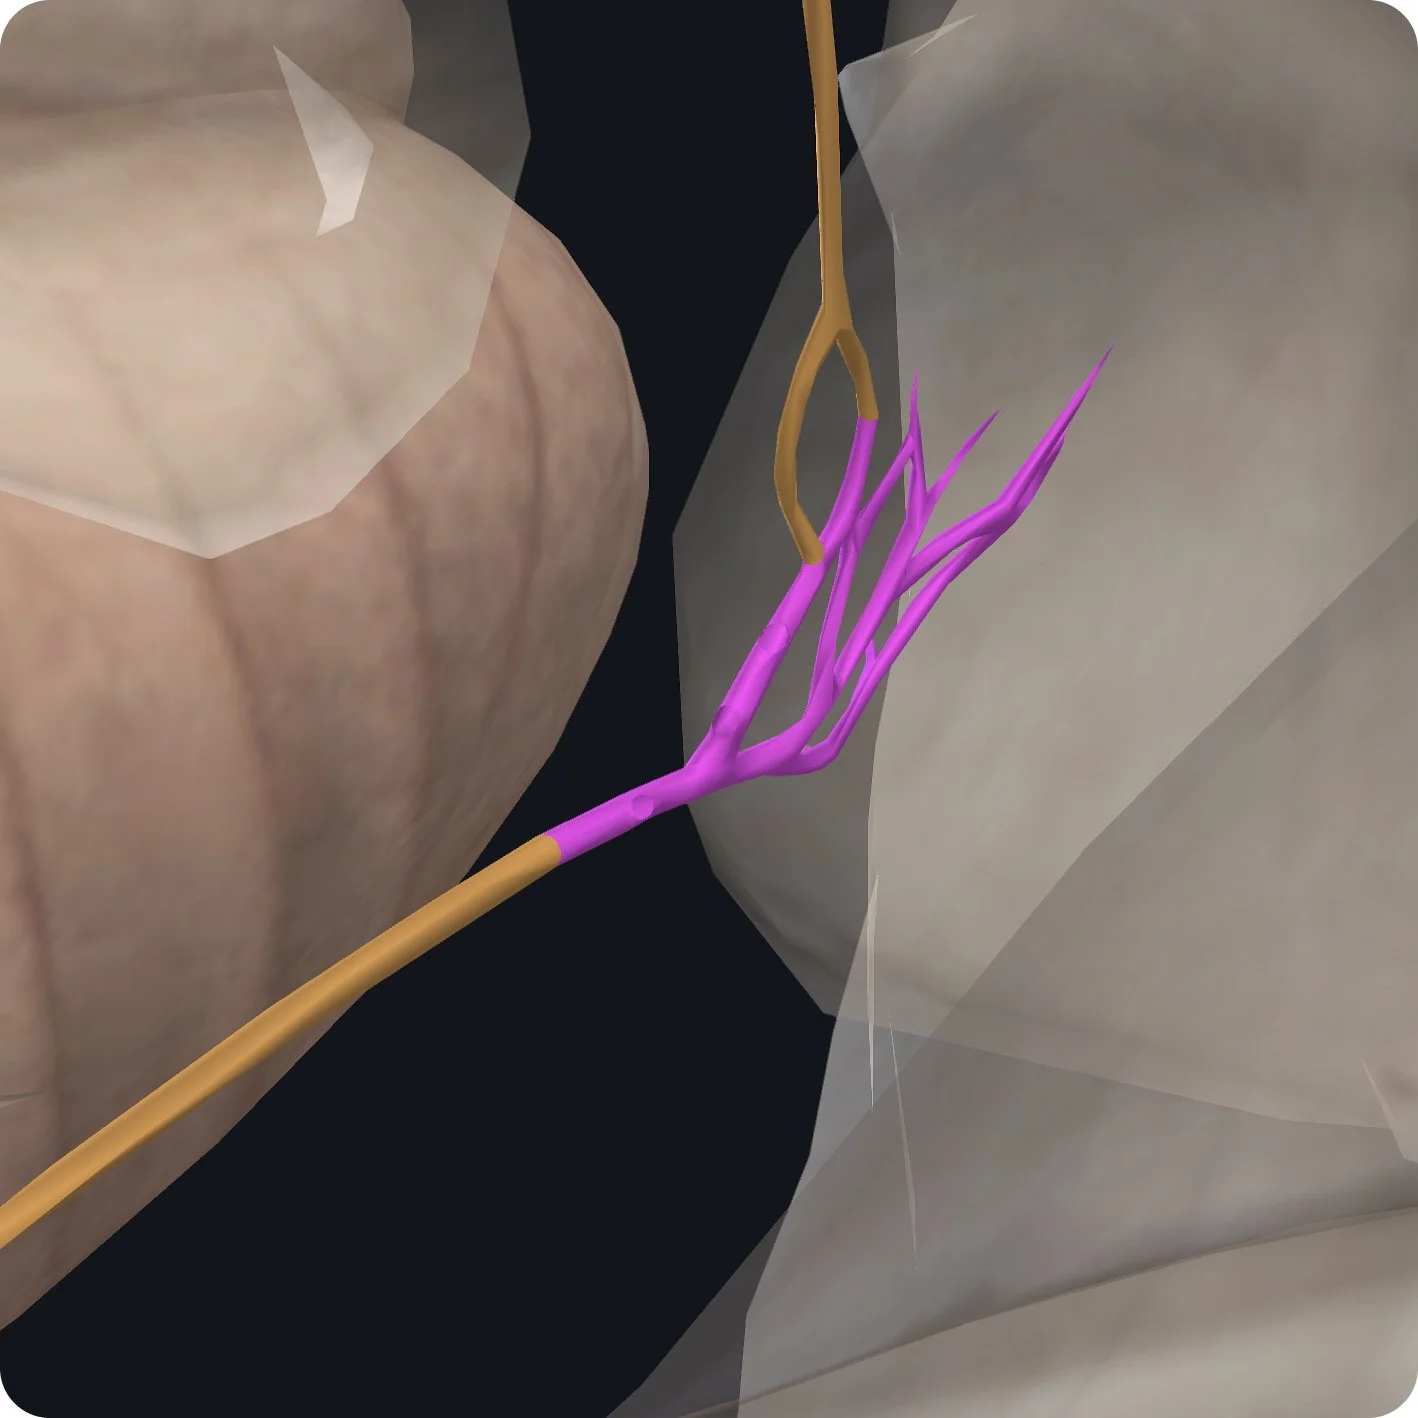

From here, it has a short intracranial journey over the lateral part of the occipital bone to the jugular foramen which is located between the temporal bone and the occipital bone.

The glossopharyngeal nerve has two ganglia the superior ganglion found within the jugular foramen followed by the inferior ganglion found below the exit of the jugular foramen.

The first of six branches arises from the inferior ganglion; it is called the tympanic nerve and it carries general visceral sensory fibers from the tympanic cavity, an auditory tube.

It also carries pre-ganglionic part sympathetic nerve fibers to the tympanic plexus.

The fibers from this plexus form the lesser petrosal nerve.

The lesser petrosal nerve carries secretary motor fibers to the parotid gland.

The remainder of the glossopharyngeal nerve runs inferior and anteriorly passing between the internal jugular vein and internal carotid artery.